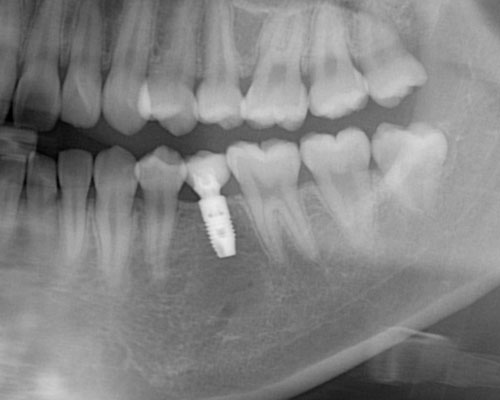

みなさんは歯を失ったら、元のように「噛めるようになりたい。」と考えられるのではないでしょうか。そして3つの選択肢のうち、ブリッジとインプラントは元の歯と同じように噛めますが、入れ歯は3割から5割の力でしか噛むことができませんので、多くの方がブリッジかインプラントのどちらにするかと悩み始めます。歯にダメージを与えないインプラントの方が良いに決まっていますが、「骨に金属のビスを打ち込む」ということに抵抗を感じる方も多いと思います。

しかし、ここで多くの方が見落としているポイントがあります。ブリッジや入れ歯を入れても、歯の根が増えるわけではないので、残っている歯の負担を軽減することはできません。これが、インプラントなら新たな支えとなるため、残っている歯の寿命を縮めることはなくなることです。

インプラントを入れようかと迷われている時、歯周病に似たインプラント周囲炎を危惧され、「歳を取ってからダメになるのじゃないか」、「介護されるころになったら磨けない」などとおっしゃる方が多いのですが、そういった方は、インプラントがダメになることばかりを考え、他の歯が割れてダメになることを考えられていないのです。

インプラントを入れるには割り切って考えることが必要です。インプラントは完全なものではありません。天然歯に比べて多くのリスクを抱えています。しかし、たとえ10年しかインプラントが保たなかったとしても、その10年間はインプラントが噛む力を負担して、他の歯にかかる力を軽減し、歯の寿命を延ばしてくれたと評価することができれば、インプラントを入れた意味は十分にあると思います。